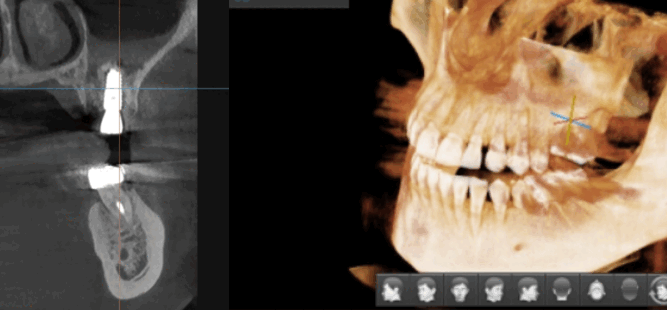

디지털 임플란트 시에는 ct 장비를 통해 분석을 하고

수술에 들어갑니다.

- 분석 > 수술

또한 임플란트가 들어갈 위치

식립 각도를 예측하여 개인 맞춤형 수술을 진행하였습니다.

위에 환자분은 잇몸 뼈가 부족하여

상악동을 들어 올리고 뼈이식을 하셔야 하는 환자분이었는데요

개인별로 다른 구강환경을 분석하여 미리 예측

잇몸도 최소로 절개할 수 있고

미리 분석한 자료를 토대로 30분 이내의 빠른 수술이 가능했습니다.